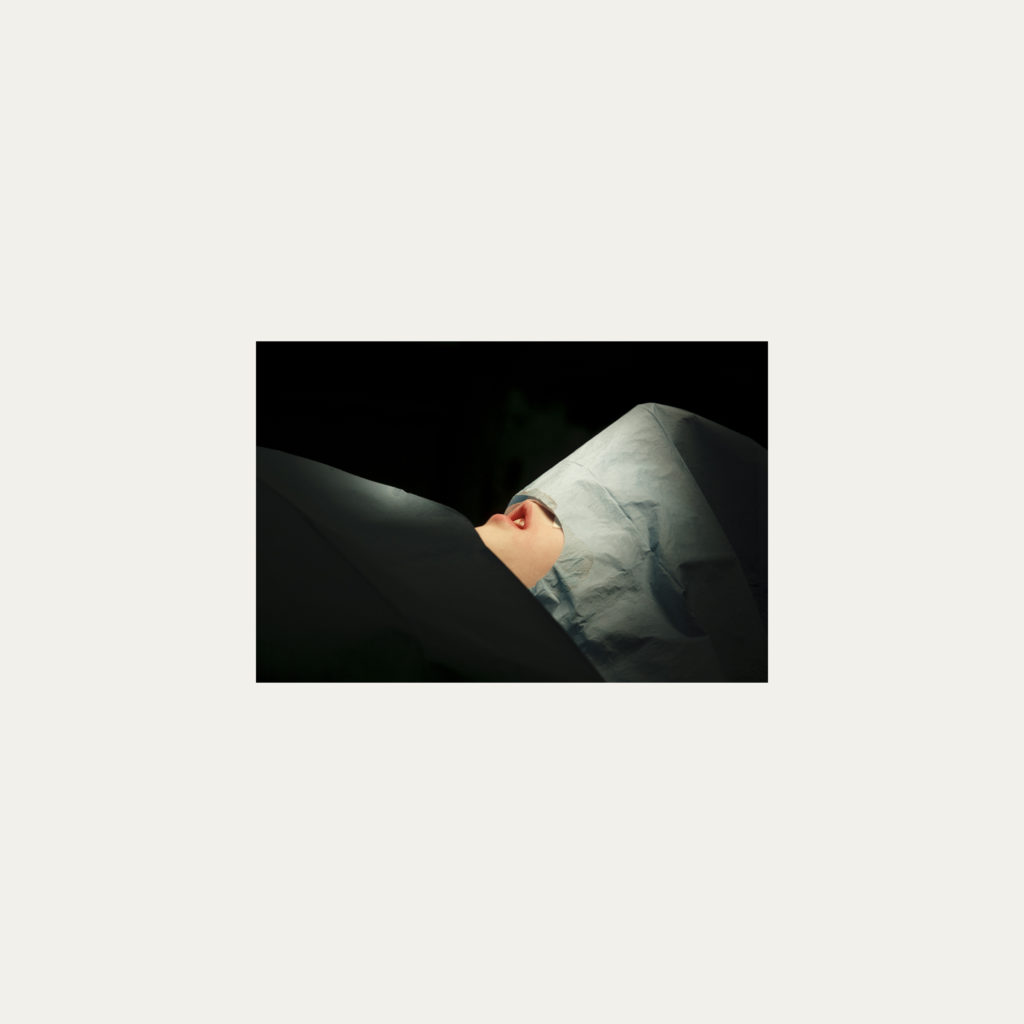

« Nature Morte » est la recherche de l’instant, pendant une intervention chirurgicale où la tête du patient opéré se retrouve seule dans le champ photographié. Aucune main intervenant, peu d’instruments chirurgicaux visibles, laissent le fragment de corps opéré existé pour lui-même. Les têtes, ainsi isolées, en deviennent presque des objets.

Cette approche est intensifiée par la présentation : dans de grands cadres carrés et passe-partout blancs, les photos de petit format font référence aux papillons épinglés de la collection d’un entomologiste.

Face à ces images, une forme de recueillement est nécessaire, s’approcher doucement pour s’approprier tous les détails des images.

Le caractère éminemment esthétique est souligné/donné par les gammes de couleur, la lumière précise sur la tête photographiée, les brillances partielles, renforçant également l’aspect pictural, les textures réelles.

L’humain présent dans ces images est celui qui rompt avec l’invisible et donne à voir l’architecture même de sa chair.